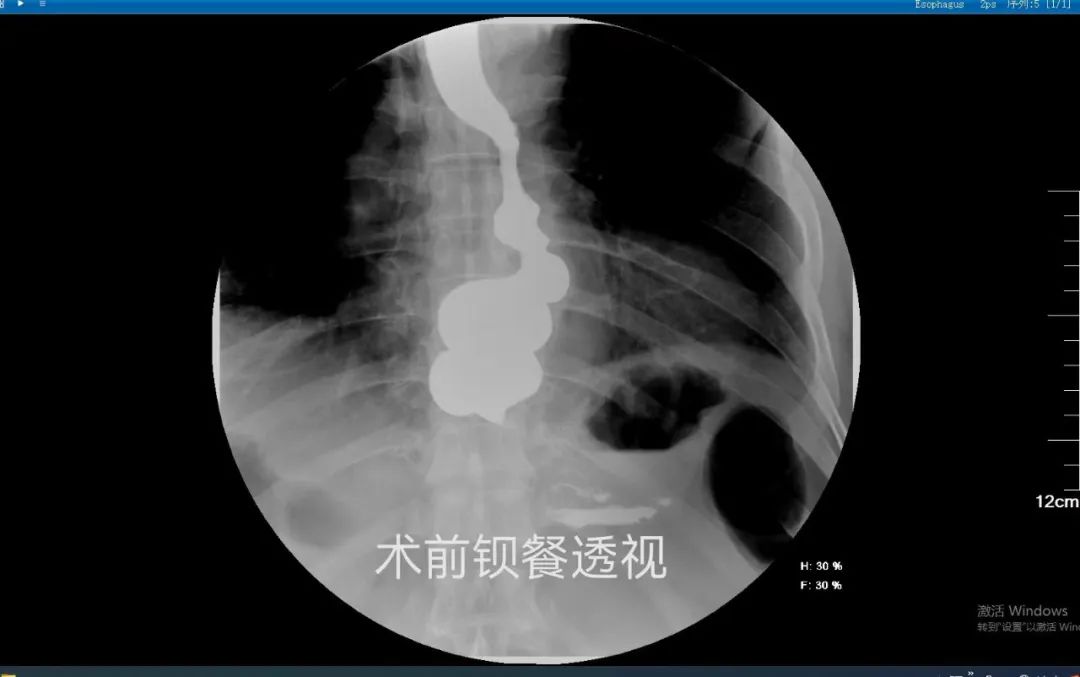

刘女士,58岁,出现进食困难近30年。她曾在多家医疗机构就诊,但病情仍反复发作并逐渐恶化,近期吞咽困难和呕吐情况加重,体重明显下降。经多方打听,她来到我院普外临床医学中心。经过详细的术前检查评估,内镜治疗组副主任孙翔宇带领团队顺利实施了经口内镜下食管括约肌切开术(POEM术)。术后恢复顺利,一周后复查碘剂食管造影显示贲门通过性良好,食管排空顺利,患者现已正常进食。